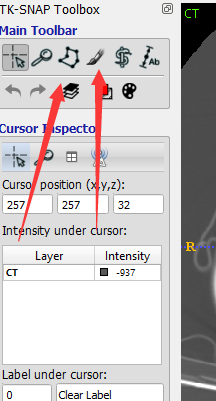

勾画对应病灶前,记得先选择病灶的类型label(软件左下角):Active Label

选择勾画工具,分为画刷和画笔两种,左侧为画笔,按住左键勾画闭合轮廓后确认即可填实、得到目标区域;右边为画刷,需要手动完整涂抹目标区域:按住左键涂抹、按住右键擦除。